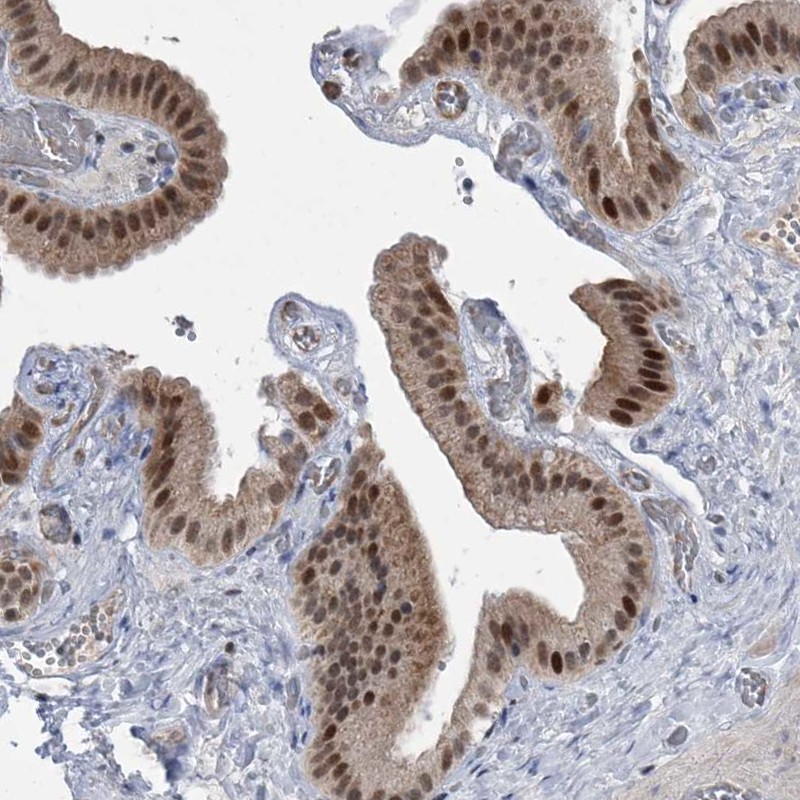

Immunohistochemical staining of human gallbladder shows strong cytoplasmic and nuclear positivity in glandular cells.